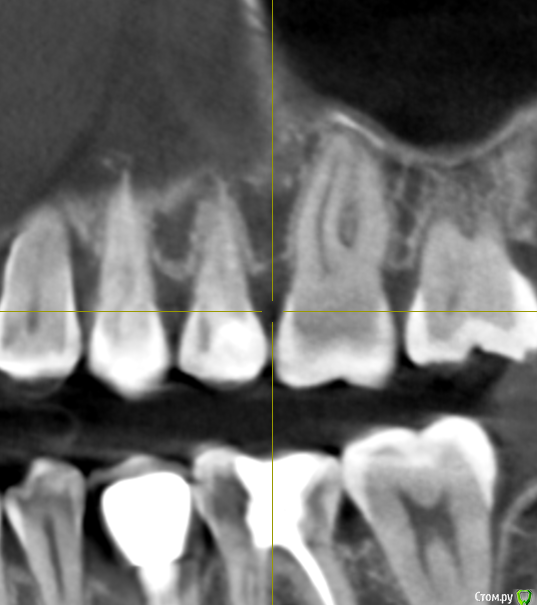

Добрый день! Два месяца назад началась моя история с зубами. Беспокоили дикие боли в зубах, как при пульпите, в 4-ке и 5-ке. Сделано было несколько прицельных и рентгеновских снимков, которые ничего не показали. Обошла пять стоматологов, никто проблем не находил, отправляли к лору или неврологу. КТ никто сделать не предложил, к сожалению. Было принято решение совместно с шестым! стоматологом депульпировать эти два зуба. При удалении нервов стоматолог сказал, что нервов уже почти нет и в 4, и в 5, сказал, что у меня хронический периодонтит, а в 4-ке стоматолог увидела на снимке (когда проверяла каналы после лечения) наружную резорбцию корня. В 5-ку поставили сразу постоянную пломбу, в 4-ке сейчас стоит временная (материал МТА). Но боль в 4-ке осталась, она не такая конечно сильная, как была, но ноющая, усиливается после горячего, после еды, в основном. И над зубом есть свищ, он не беспокоит и не болит при надавливании (стоматолог говорит, что это материал под десной, из-за резорбции) Врач говорит, что все пройдет, и через 2 месяца ставим постоянную пломбу, но болит уже месяц. Я сама сделала КТ, очень прошу вас посмотреть и подсказать, как действовать дальше? Может проще удалить этот зуб и поставить имплантат?